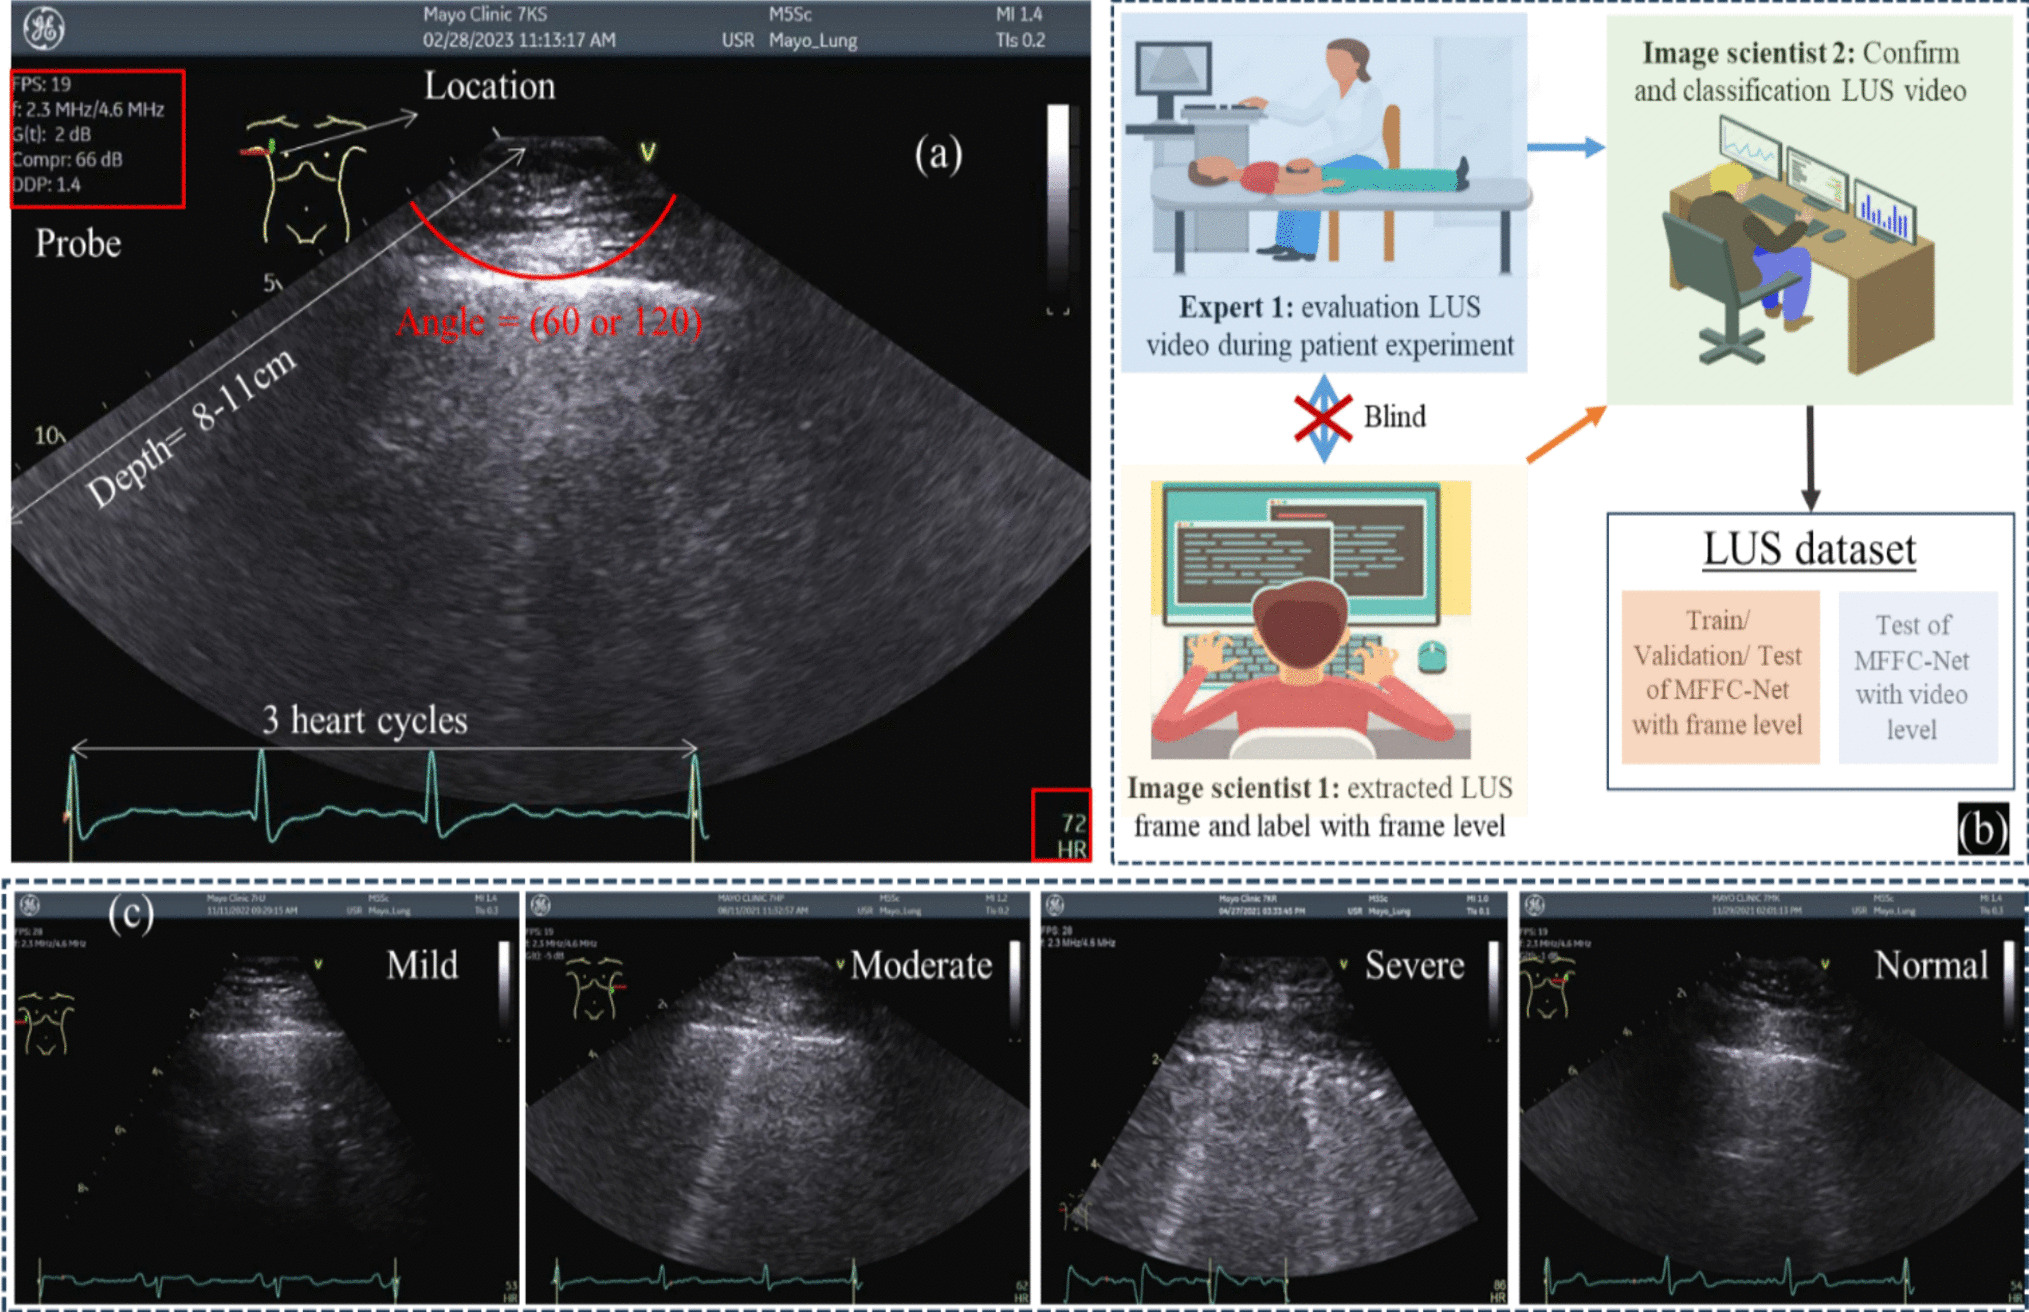

The dataset used in this study consists of videoendoscopic frames of patients treated at the Unit of Otorhinolaryngology-Head and Neck Surgery, University of Brescia, Italy. Data were acquired using three different Olympus laryngoscopes (models ENF-VH, ENF-VQ, and ENF-V2), following the principles of the Helsinki Declaration, and approval was obtained by the local ethical committee. A total of 471 endoscopic images from 124 patients were collected from a dedicated archive and anonymized. Of these images, 114 were acquired from 28 subjects diagnosed with squamous cell carcinoma. The number of images per patient ranged from 1 to 5 with a median of 3, ensuring a comparable distribution of patient data.

Figure 1 shows some of the challenges in the dataset, including varying illumination levels, presence of both white-light and narrow-band frames, presence of noise, blurring and specular reflection, varying pose of the VF and different fields of view, and frames from pathological subjects. Another challenge in the dataset is related to the AGA variability, which has a median value of \(15.12^\), with first quartile (Q1)=8.09 and third quartile (Q3)=22.19, and an interquartile range (IQR)=14.10 (minimum AGA value=\(1.32^\), maximum AGA value=\(91.85^\)).

Frames annotation was performed using Label-studioFootnote 1 by an expert laryngologist with more than ten years of experience. The keypoints were assigned with visibility flags according to the COCO Keypoint detection annotation format: 0 for keypoints not present in the image (which do not occur in our dataset), 1 for keypoints present in the image but not visible (possibly occluded by other anatomical structures), and 2 for clearly visible keypoints.